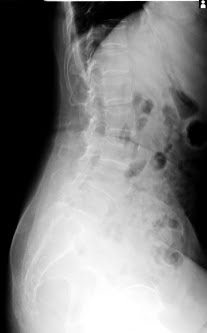

On 13.1.2022 : Erect PA

On 17.1.2022 : LAT